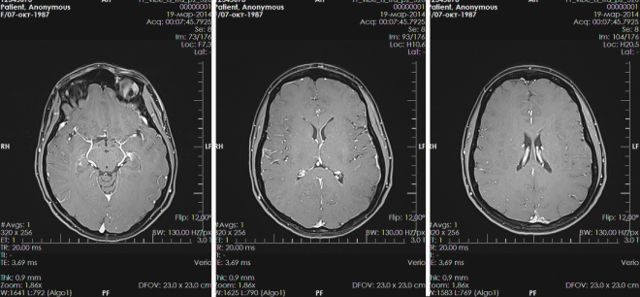

- Ультразвуковое исследование головного мозга. В неврологии оно также называется нейросонографией. Этот метод достаточно безопасный и может применяться даже для малышей в первые месяцы жизни. От обследования нет никаких болезненных ощущений. Для определения диагноза достаточно 15-25 минут.

- Компьютерная томография (или КТ). Исследование дает высокую лучевую нагрузку. Выполнять его для скрининга кистозных образований не следует. Используется данный метод только в сложных клинических случаях, когда постановка диагноза затруднена. Исследование дает полную картину имеющихся в головном мозге аномалий и анатомических дефектов.

- Магнитно-резонансная томография (или МРТ). Отзывы после проведения данного исследования самые положительные. В большинстве случаев именно с помощью МРТ удалось установить наличие кистозных образований в головном мозге. Метод отличается высокой разрешающей способностью и позволяет успешно выявлять кисты даже самых маленьких размеров. В сложных диагностических случаях прибегают к предварительному введению контраста, позволяющего устанавливать диагноз более точно.

Удаление выполняют после полной тщательной ультразвуковой диагностики (нейросонографии), МРТ. Занимаются удалением детские нейрохирурги. Диагноз хориоидальной кисты – это не приговор. При своевременном обращении за помощью оперативное вмешательство позволяет полностью излечить малыша.

В случае установления диагноза киста субэпендимального типа возникает необходимость проводить МРТ-исследование или МР-диагностику не реже двух раз в течение года. Хотя образование кистозных разрастаний данного типа медики считают положительным процессом. Но все же возможны появления резкого повышенного давления внутри полости разросшейся кисты при каких-либо осложнениях.